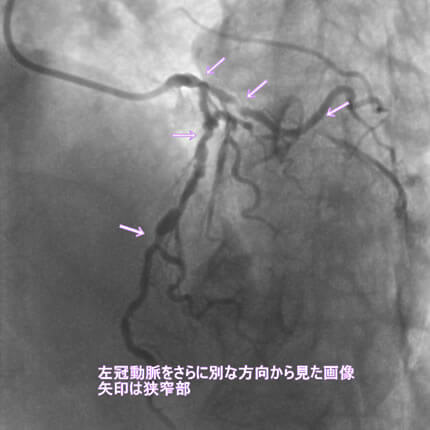

危険因子が特に複合的にあると動脈硬化は加速します。今回は、動脈硬化が加速するとどうなるか、実際の症例でお示しします。なお、お見せします画像は、すべて動画から静止画像にしています。実際には冠動脈造影は動画で見ます。

また、動脈硬化は冠動脈だけに生じる訳ではないことも示したいと思います。冠動脈に病変がある方は他の動脈にも強い動脈硬化を認めることが多いのです。具体的には腹部大動脈瘤、胸部大動脈瘤、脳梗塞、脳出血、下肢動脈閉塞などを合併します。逆にこれらの病気が見つかってそれから冠動脈疾患が見つかることも結構あります。血管は三次元構造なので色々な方向から撮影して血管形態を確かめます。同じ血管を左右上下や斜め方向から撮影します。

1番目の患者さんは80歳の男性です。この方の危険因子は高血圧、高脂血症、喫煙です。この方の冠動脈造影と腹部CT画像を示します。図1-1から1-8の画像は全て全てこの患者さんの画像です。

図1-3 左冠動脈造影像

図1-4 左冠動脈造影像

よく解らないと思いますが、冠動脈に多数の狭窄があることと冠動脈が「こぶ状変化(医学用語で瘤状変化)」を生じているのが解ると思います。